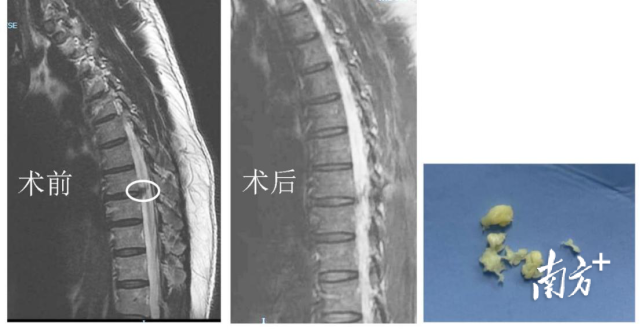

近1周,何先生疼痛剧烈,夜间甚至无法平躺睡觉,连续几个晚上只能坐着睡觉,让其苦不堪言。他再次赶往当地另外一家医院行胸椎核磁共振检查,影像结果提示,胸8/9间隙有椎间盘突出。在朋友的推荐下,他来到暨南大学附属第一医院脊柱外科吴昊主任医师的门诊看诊。

在详细查体、询问病史和分析影像学检查后,吴昊主任医师很快发现何先生的外院磁共振结果提示胸8/9椎间盘右侧有较大的髓核突出,相应节段的神经受压,与何先生胸痛的层面比较吻合。

脊柱UBE微创手术操作时间不到40分钟,术中探查胸椎间盘有小破口,较大髓核脱出,压迫神经,术中予髓核摘除,神经探查减压,纤维环成形处理,当天麻醉过后,何先生自诉右侧胸痛不舒适感明显缓解,术后第一天予拔除引流管,指导下地行走。他喜逐颜开:“我终于可以睡个好觉了!”